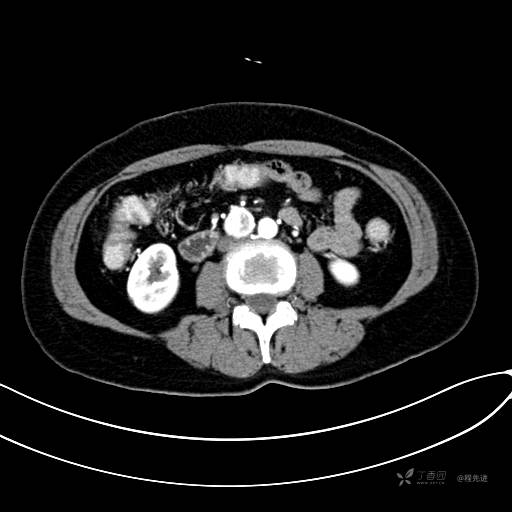

CT增强门脉期